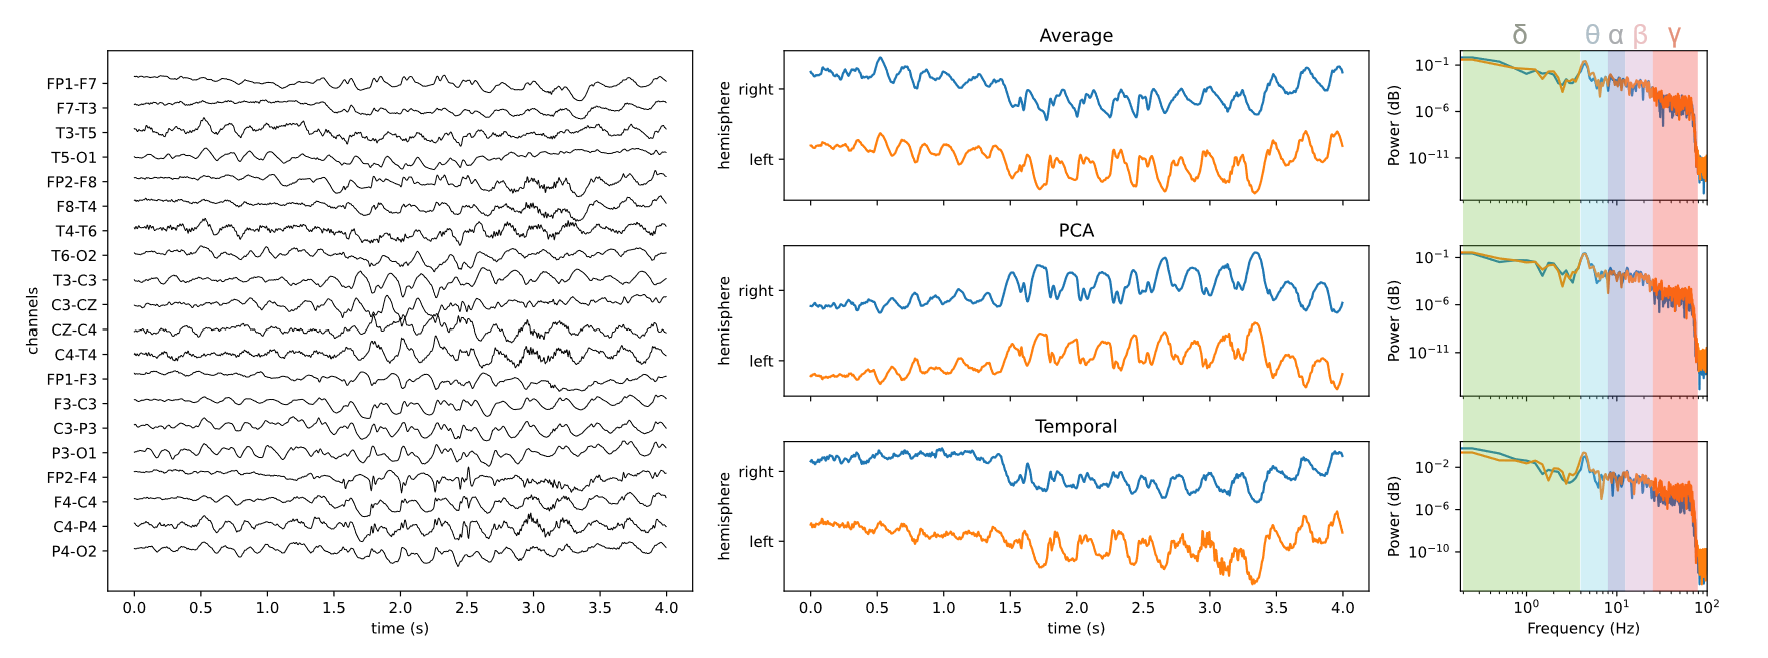

Thesis "Multiscale Modeling of Epileptic Seizure Dynamics" under the supervision of Viktor Jirsa (theoretical physics) and Christophe Bernard (neurophysiology).

Data engineering, analysis of multimodal dataset, and multiscale modeling of neurostimulation in obsessive-compulsive disorders.

Check out some of my work